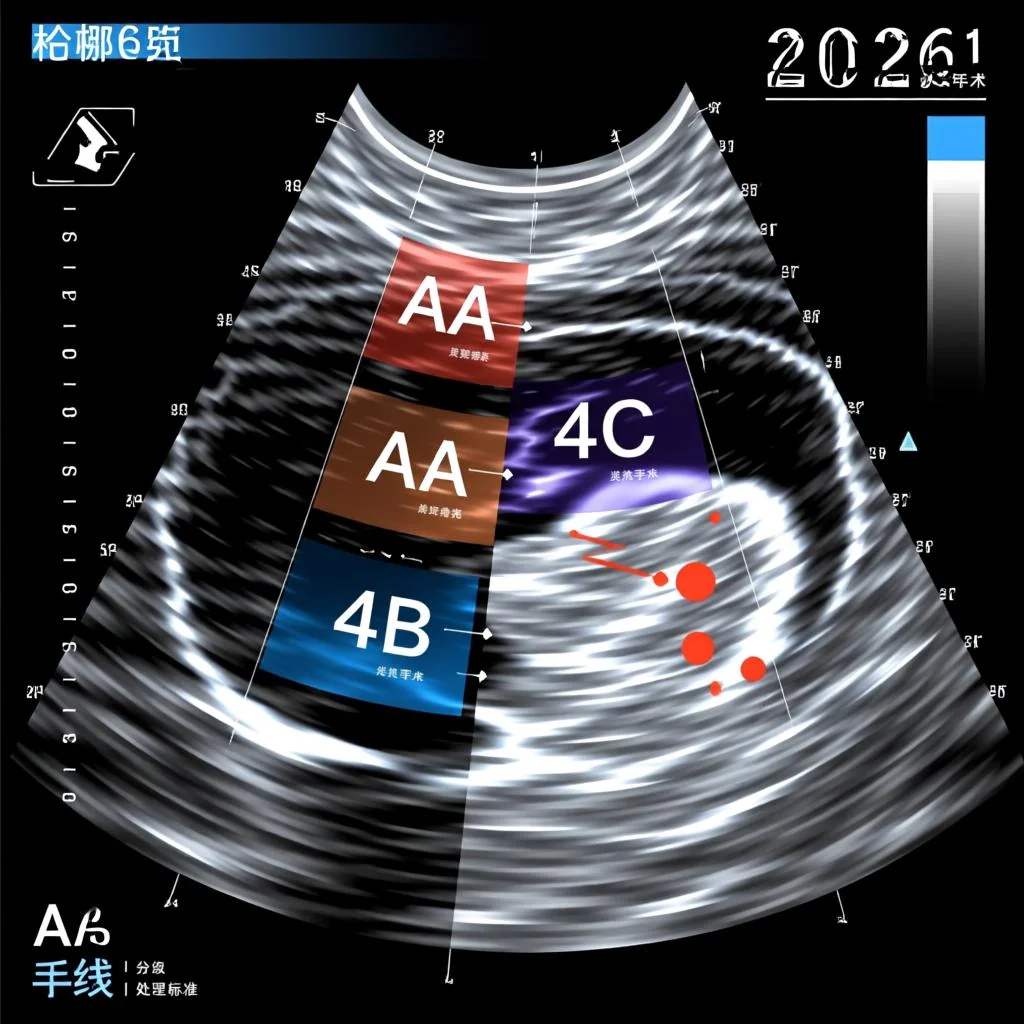

甲状腺4类结节,在TI-RADS分级中特指“可疑恶性”的一类结节。目前我国通用的中国版甲状腺结节超声恶性风险分层(C-TIRADS)和欧美版的ACR-TIRADS都将4类作为临界类别。它不是一个单一的等级,而是为了更精确地描述风险程度,被细分为4A、4B、4C三个亚级。

- 甲状腺4A类结节:具有1项恶性超声特征。恶性风险概率约为5%-10%。

- 甲状腺4B类结节:具有2项恶性超声特征。恶性风险概率约为10%-50%。

- 甲状腺4C类结节:具有3-4项恶性超声特征。恶性风险概率约为50%-85%。